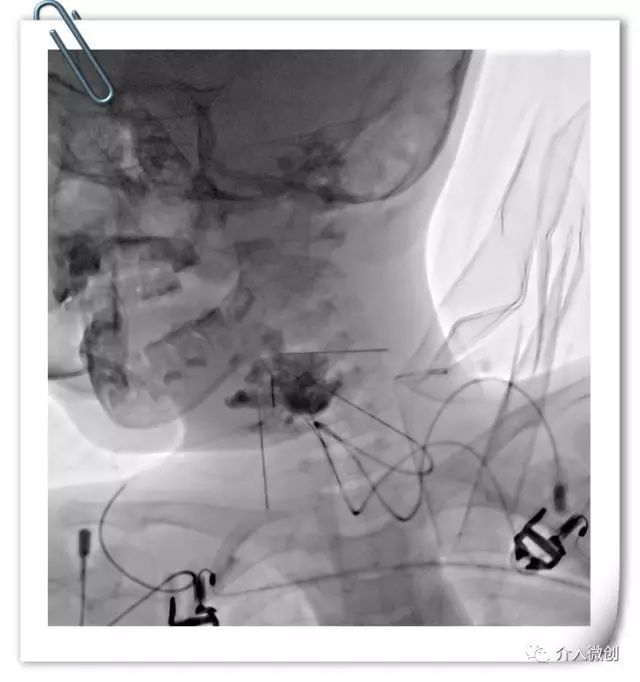

DSA引导下经皮穿刺囊腔,抽吸囊液,囊腔内注射硬化剂硬化治疗。

DSA引导下经皮穿刺硬化注射治疗。